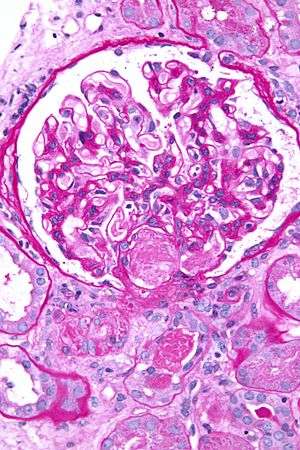

A glomerulus (RP English pronunciation: /ɡlɒˈmɛr(j)uːləs/, American /ɡlɒˈmɛrələs/) is a network (as a tuft) of capillaries located at the beginning of a nephron in the kidney. It serves as the first stage in the filtering process of the blood carried out by the nephron in its formation of urine.

The glomerulus is surrounded by a cup-like sac known as Bowman's capsule. The blood plasma is filtered through the capillaries of the glomerulus into the capsule. The Bowman's capsule empties the filtrate into the proximal tubule that is also part of the duct system of the nephron.

A glomerulus and its surrounding Bowman's capsule constitute a renal corpuscle, the basic filtration unit of the kidney.[1] The rate at which blood is filtered through all of the glomeruli, and thus the measure of the overall renal function, is the glomerular filtration rate (GFR).

The glomerulus is a tuft of small blood vessels called capillaries located within Bowman's capsule within the kidney.[1] Between the capillaries and Bowman's capsule lies the mesangium. Blood enters the capillaries of the glomerulus by a single arteriole called an afferent arteriole and leaves by an efferent arteriole.[2] The capillaries are lined by a layer of cells (an endothelium) that has a unique structure, allowing blood components to be filtered, and resulting ultimately in the formation of urine.